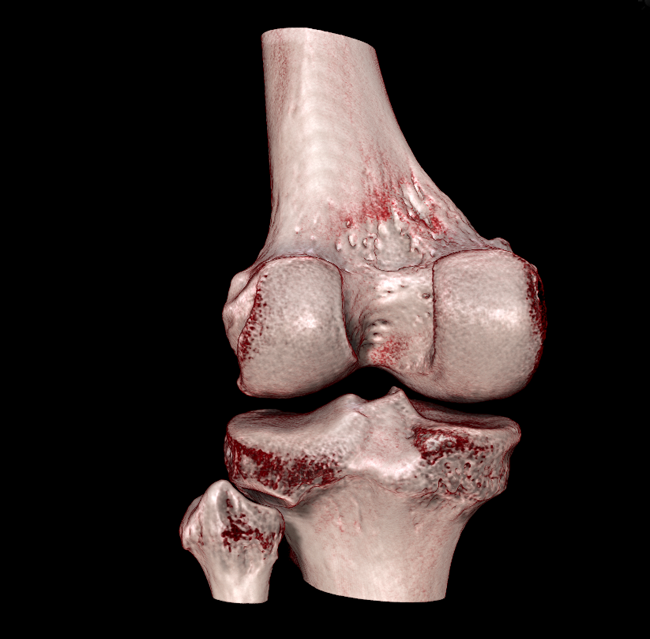

HRCT

High Resolution Computed Tomography. Outstanding image quality with a voxel size up to 100 µm